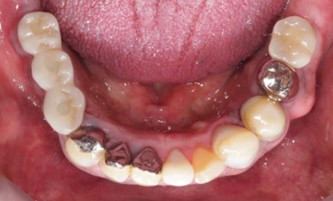

70代 女性

治療前

- 70代/女性

- 患者の具体的な症状

- 下顎の奥歯が義歯で噛みづらいため、インプラント治療を希望

- 検査方法

- コーンビームCT、レントゲン撮影

- 診断結果

- 左下6欠損

- 治療詳細

- 左下6インプラント埋入1本、骨造成なし、局所麻酔

- 通院回数

- 8回

- 治療期間

- 6か月